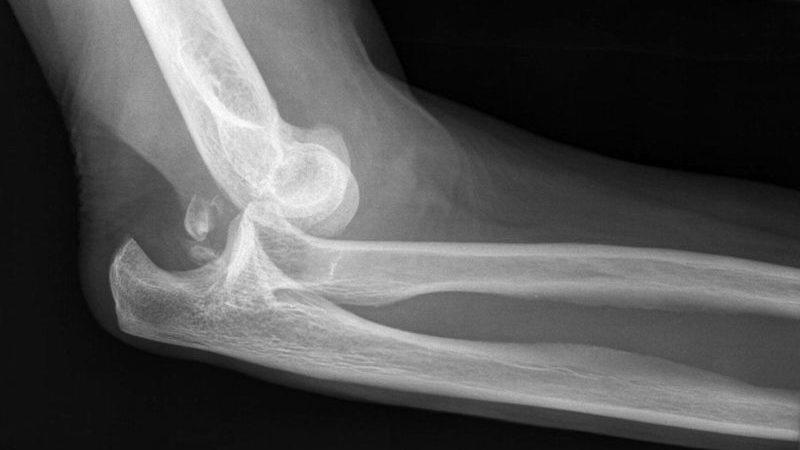

Врачи подчеркивают, что лечение вывиха локтевого сустава должно начинаться с немедленной медицинской помощи. Первым шагом является иммобилизация поврежденной конечности, чтобы предотвратить дальнейшие травмы. Специалисты рекомендуют обратиться в травмпункт для проведения рентгенографии, которая поможет исключить сопутствующие переломы. В большинстве случаев вывих вправляется вручную, однако в сложных ситуациях может потребоваться хирургическое вмешательство. После вправления важно начать реабилитацию, включая физиотерапию, чтобы восстановить подвижность и силу сустава. Врачи также акцентируют внимание на необходимости следить за состоянием сустава в процессе восстановления, чтобы избежать возможных осложнений.

Медицинская помощь при вывихе локтевого сустава включает его вправление под местной анестезией. Крайне важно правильно установить диагноз с помощью рентгенографии, так как в некоторых случаях травма может сопровождаться внутрисуставным переломом.